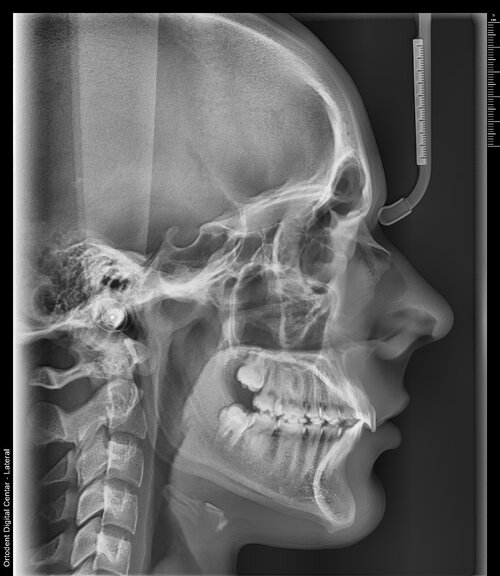

i am getting braces with elastic bands, no extractions but what else should i do to try to ascend because i really feel chopped especially my side profile, i feel like my maxilla is recessed and downgrown and it makes me look terrible and also it comes into play that my lower jaw is a bit back because of my overjeet so idk what i should do. it may just be over for me